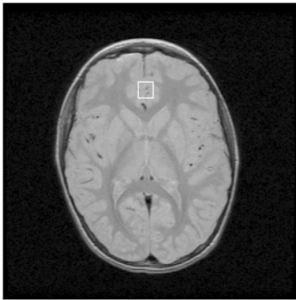

مسح الدماغ بجهاز MRS:

لفهم سبب لجوء واتانابي وزملاؤه إلى التحليل الطيفي بالرنين المغناطيسي (MRS). عندما يتعلق الأمر بمسح الدماغ استخدام الرنين المغناطيسي الطيفي (MRS) بدلا من أجهزة (MRI) الوظيفية والمعروفة بـ (FMRI)، لأن أجهزة (FMRI) تقيس وظائف الدماغ بتعقب الأوكسجين في الدماغ، فالمناطق التي تبذل جهد أكبر تستهلك أوكسجين أكثر, لذلك من الممكن ربط وظيفة الدماغ باستهلاك الأوكسجين, في المقابل أجهزة (MRS) تتعقب المواد الكيميائية مثل الكربون والنيتروجين الموجودة في النواقل العصبية للدماغ، وتسمح للباحثين تقييم أي نواقل العصبية في الدماغ.

باستخدام جهاز (MRS)، كرر الباحثون التجارب السابقة ولكن مع تغييرين. أولاً، تم تدريب المجموعتين على الحالة المعتادة (ثمانية دورات)، أو الإفراط في التعلم (ستة عشر دورة) ، ولكن بدون تدريب ثانٍ. وقبل الاختبار الأول والتدريب، قام الباحثون بمسح أدمغة المتدربين في جهاز (MRS). قام الباحثون أيضًا بمسح أدمغة المتدربين بعد 30 دقيقة من التدريب، ومرة أخرى بعد 3.5 ساعات من التدريب. ثم تم إجراء الاختبار الآخر مرة أخرى في اليوم الثاني.

ما وجده واتانابي هو أنك إذا لم تتعلم بشكل مفرط، فإن الدماغ لديه كميات أعلى من الغلوتامات. الغلوتامات مادة كيميائية تجعل دماغك أكثر مرونة أو أكثر مهارة في التعلم. لكن الإفراط في التعلم يقلل من كمية الغلوتامات ويزيد من كمية GABA (حمض الغاما-أمينوبيوتيريك)، وهي مادة كيميائية تعمل على استقرار الدماغ.